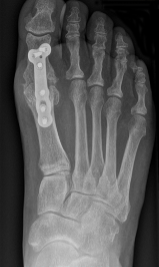

Bild: Universitätsklinik Balgrist

Bei fortgeschrittener Arthrose im Grosszehengrundgelenk ist die Versteifung nach wie vor der operative Goldstandard *. Bei diesem Eingriff wird der noch vorhandene Restknorpel entfernt und der angrenzende Knochen zur besseren Heilung «angefrischt». Dazu wird die Knochenschicht unter dem Knorpel mikroskopisch klein aufgebrochen, um das Zusammenwachsen zu fördern. Mittels Schrauben oder einer Platte wird der Knochen wieder fixiert. Durch das Zusammenheilen des Gelenks verschwinden in der Regel die arthrosetypischen Beschwerden.

Der Eingriff erfordert üblicherweise einen stationären Aufenthalt von zwei bis drei Tagen. In den ersten zwei Wochen sollte der Fuss zur besseren Wundheilung hochgelagert werden. Die Mobilisation in der Physiotherapie erfolgt in einem Therapieschuh, der die Arthrodese schützt. Nach sechs Wochen findet eine Nachkontrolle mit klinischer Untersuchung und einer Röntgenaufnahme statt. Je nachdem wie der Knochen zusammenheilt, muss der Fuss weiterhin auf einer harten Sohle ruhiggestellt werden.